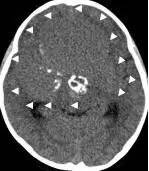

病例1:患儿男性,9岁。因反复出现意识丧失、视力下降半年收入院。入院后CT及 MRI显示颅内有形态不规则、“超大型”的颅咽管瘤,最大径约10厘米,见图1、图2。

图1.术前CT显示典型的囊性颅咽管瘤

白色三角显示肿瘤边界